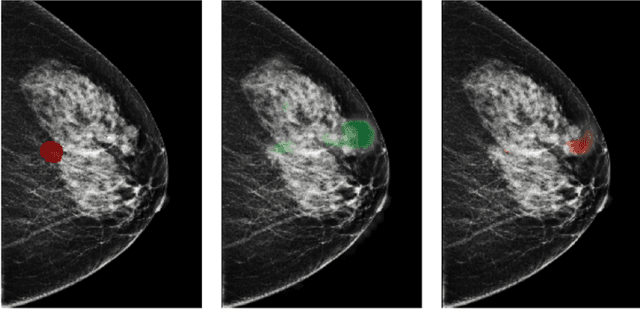

Abstract:Deep neural networks (DNNs) show promise in image-based medical diagnosis, but cannot be fully trusted since their performance can be severely degraded by dataset shifts to which human perception remains invariant. If we can better understand the differences between human and machine perception, we can potentially characterize and mitigate this effect. We therefore propose a framework for comparing human and machine perception in medical diagnosis. The two are compared with respect to their sensitivity to the removal of clinically meaningful information, and to the regions of an image deemed most suspicious. Drawing inspiration from the natural image domain, we frame both comparisons in terms of perturbation robustness. The novelty of our framework is that separate analyses are performed for subgroups with clinically meaningful differences. We argue that this is necessary in order to avert Simpson's paradox and draw correct conclusions. We demonstrate our framework with a case study in breast cancer screening, and reveal significant differences between radiologists and DNNs. We compare the two with respect to their robustness to Gaussian low-pass filtering, performing a subgroup analysis on microcalcifications and soft tissue lesions. For microcalcifications, DNNs use a separate set of high frequency components than radiologists, some of which lie outside the image regions considered most suspicious by radiologists. These features run the risk of being spurious, but if not, could represent potential new biomarkers. For soft tissue lesions, the divergence between radiologists and DNNs is even starker, with DNNs relying heavily on spurious high frequency components ignored by radiologists. Importantly, this deviation in soft tissue lesions was only observable through subgroup analysis, which highlights the importance of incorporating medical domain knowledge into our comparison framework.

Abstract:Breast cancer is the most common cancer in women, and hundreds of thousands of unnecessary biopsies are done around the world at a tremendous cost. It is crucial to reduce the rate of biopsies that turn out to be benign tissue. In this study, we build deep neural networks (DNNs) to classify biopsied lesions as being either malignant or benign, with the goal of using these networks as second readers serving radiologists to further reduce the number of false positive findings. We enhance the performance of DNNs that are trained to learn from small image patches by integrating global context provided in the form of saliency maps learned from the entire image into their reasoning, similar to how radiologists consider global context when evaluating areas of interest. Our experiments are conducted on a dataset of 229,426 screening mammography exams from 141,473 patients. We achieve an AUC of 0.8 on a test set consisting of 464 benign and 136 malignant lesions.

Abstract:Deep neural networks (DNNs) show promise in breast cancer screening, but their robustness to input perturbations must be better understood before they can be clinically implemented. There exists extensive literature on this subject in the context of natural images that can potentially be built upon. However, it cannot be assumed that conclusions about robustness will transfer from natural images to mammogram images, due to significant differences between the two image modalities. In order to determine whether conclusions will transfer, we measure the sensitivity of a radiologist-level screening mammogram image classifier to four commonly studied input perturbations that natural image classifiers are sensitive to. We find that mammogram image classifiers are also sensitive to these perturbations, which suggests that we can build on the existing literature. We also perform a detailed analysis on the effects of low-pass filtering, and find that it degrades the visibility of clinically meaningful features called microcalcifications. Since low-pass filtering removes semantically meaningful information that is predictive of breast cancer, we argue that it is undesirable for mammogram image classifiers to be invariant to it. This is in contrast to natural images, where we do not want DNNs to be sensitive to low-pass filtering due to its tendency to remove information that is human-incomprehensible.